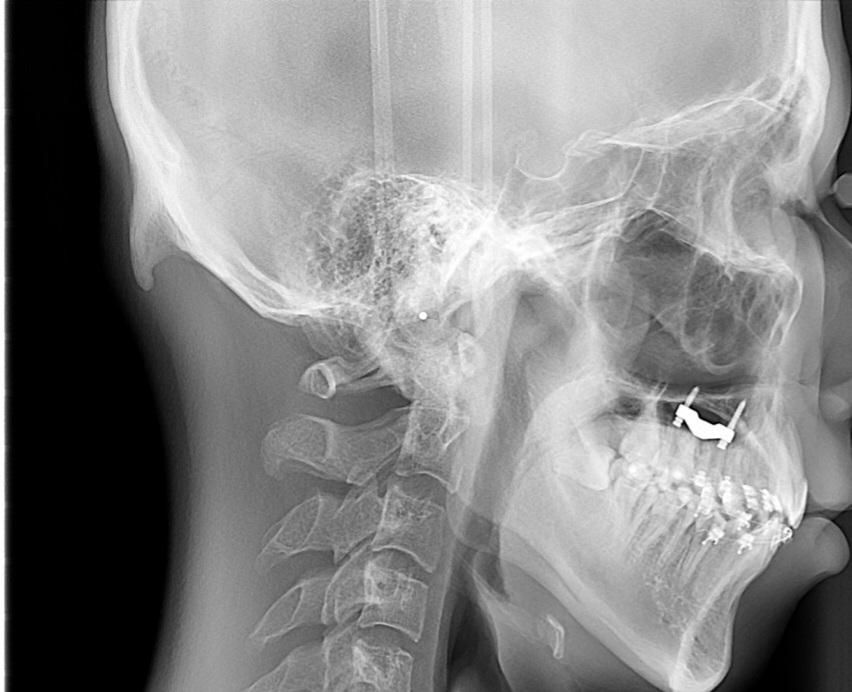

외후두융기(External occipital protuberance)는 후두골 뒤쪽 정중앙에 위치한 정상적인 해부학적 돌출입니다. 개인마다 크기 차이가 있으며, 일부에서는 비교적 크게 돌출되어 보일 수 있습니다. 첨부된 측면 두개골 X선에서도 후두부 뒤쪽에 비교적 뚜렷한 골성 돌출이 보이지만, 단순히 크기가 크다는 이유만으로 병적 상태로 판단되지는 않습니다.

이 구조는 목 뒤 근육과 인대가 부착되는 부위이기 때문에 근육 사용이 많거나 장기간 자세 부담이 있는 경우 돌출이 더 도드라져 보일 수 있습니다. 최근 스마트폰 사용 증가와 관련하여 후두부 돌출이 커 보인다는 보고도 있으나, 실제로 뼈가 새로 자란다기보다는 원래 존재하던 구조가 강조되어 보이는 경우가 많습니다. 단순 돌출 자체는 신경이나 뇌 구조와 직접적인 연관이 없어 위험한 상태로 보지는 않습니다.

치료는 일반적으로 필요하지 않습니다. 다만 다음 상황에서는 진료가 권장됩니다. 돌출 부위 통증이 지속되는 경우, 만지면 염증이나 부종이 동반되는 경우, 크기가 빠르게 증가하는 경우입니다. 이런 경우에는 단순 골돌기인지, 골종 같은 양성 골종양인지 감별을 위해 추가 영상검사가 필요할 수 있습니다. 대부분은 촉진과 영상으로 쉽게 구분됩니다.

통증이 없다면 특별한 처치 없이 경과 관찰만 하는 경우가 일반적입니다. 만약 외관상 매우 커서 불편하거나 압통이 지속될 경우에는 드물게 성형외과 또는 신경외과에서 골 돌출을 절제하는 수술적 교정이 시행되기도 합니다. 그러나 이는 미용적 이유나 지속적인 통증이 있을 때 제한적으로 고려됩니다.